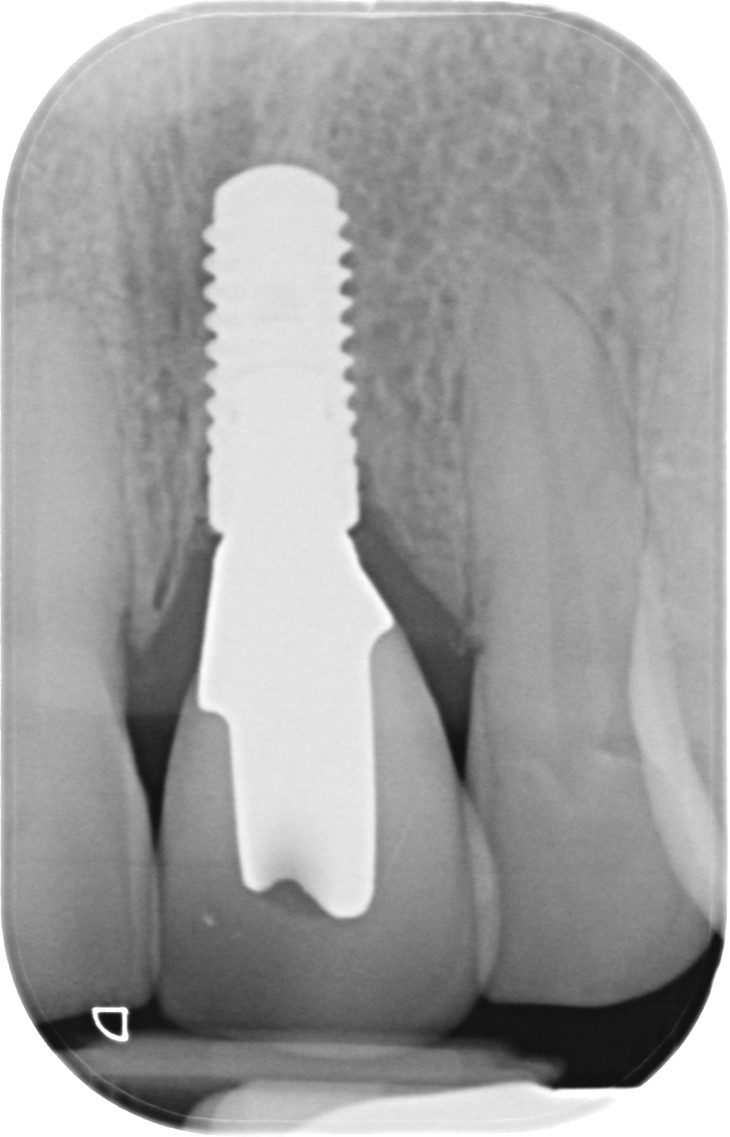

Immediate implant placement with cerabone® and mucoderm® - Dr. F. Rossi - X-ray of tooth 11Immediate implant placement with cerabone® and mucoderm® - Dr. F. Rossi

Immediate implant placement with cerabone® and mucoderm® - Dr. F. Rossi - Control x-rayImmediate implant placement with cerabone® and mucoderm® - Dr. F. Rossi

Immediate implant placement with cerabone® and mucoderm® - Dr. F. Rossi - Final x-ray controlImmediate implant placement with cerabone® and mucoderm® - Dr. F. Rossi